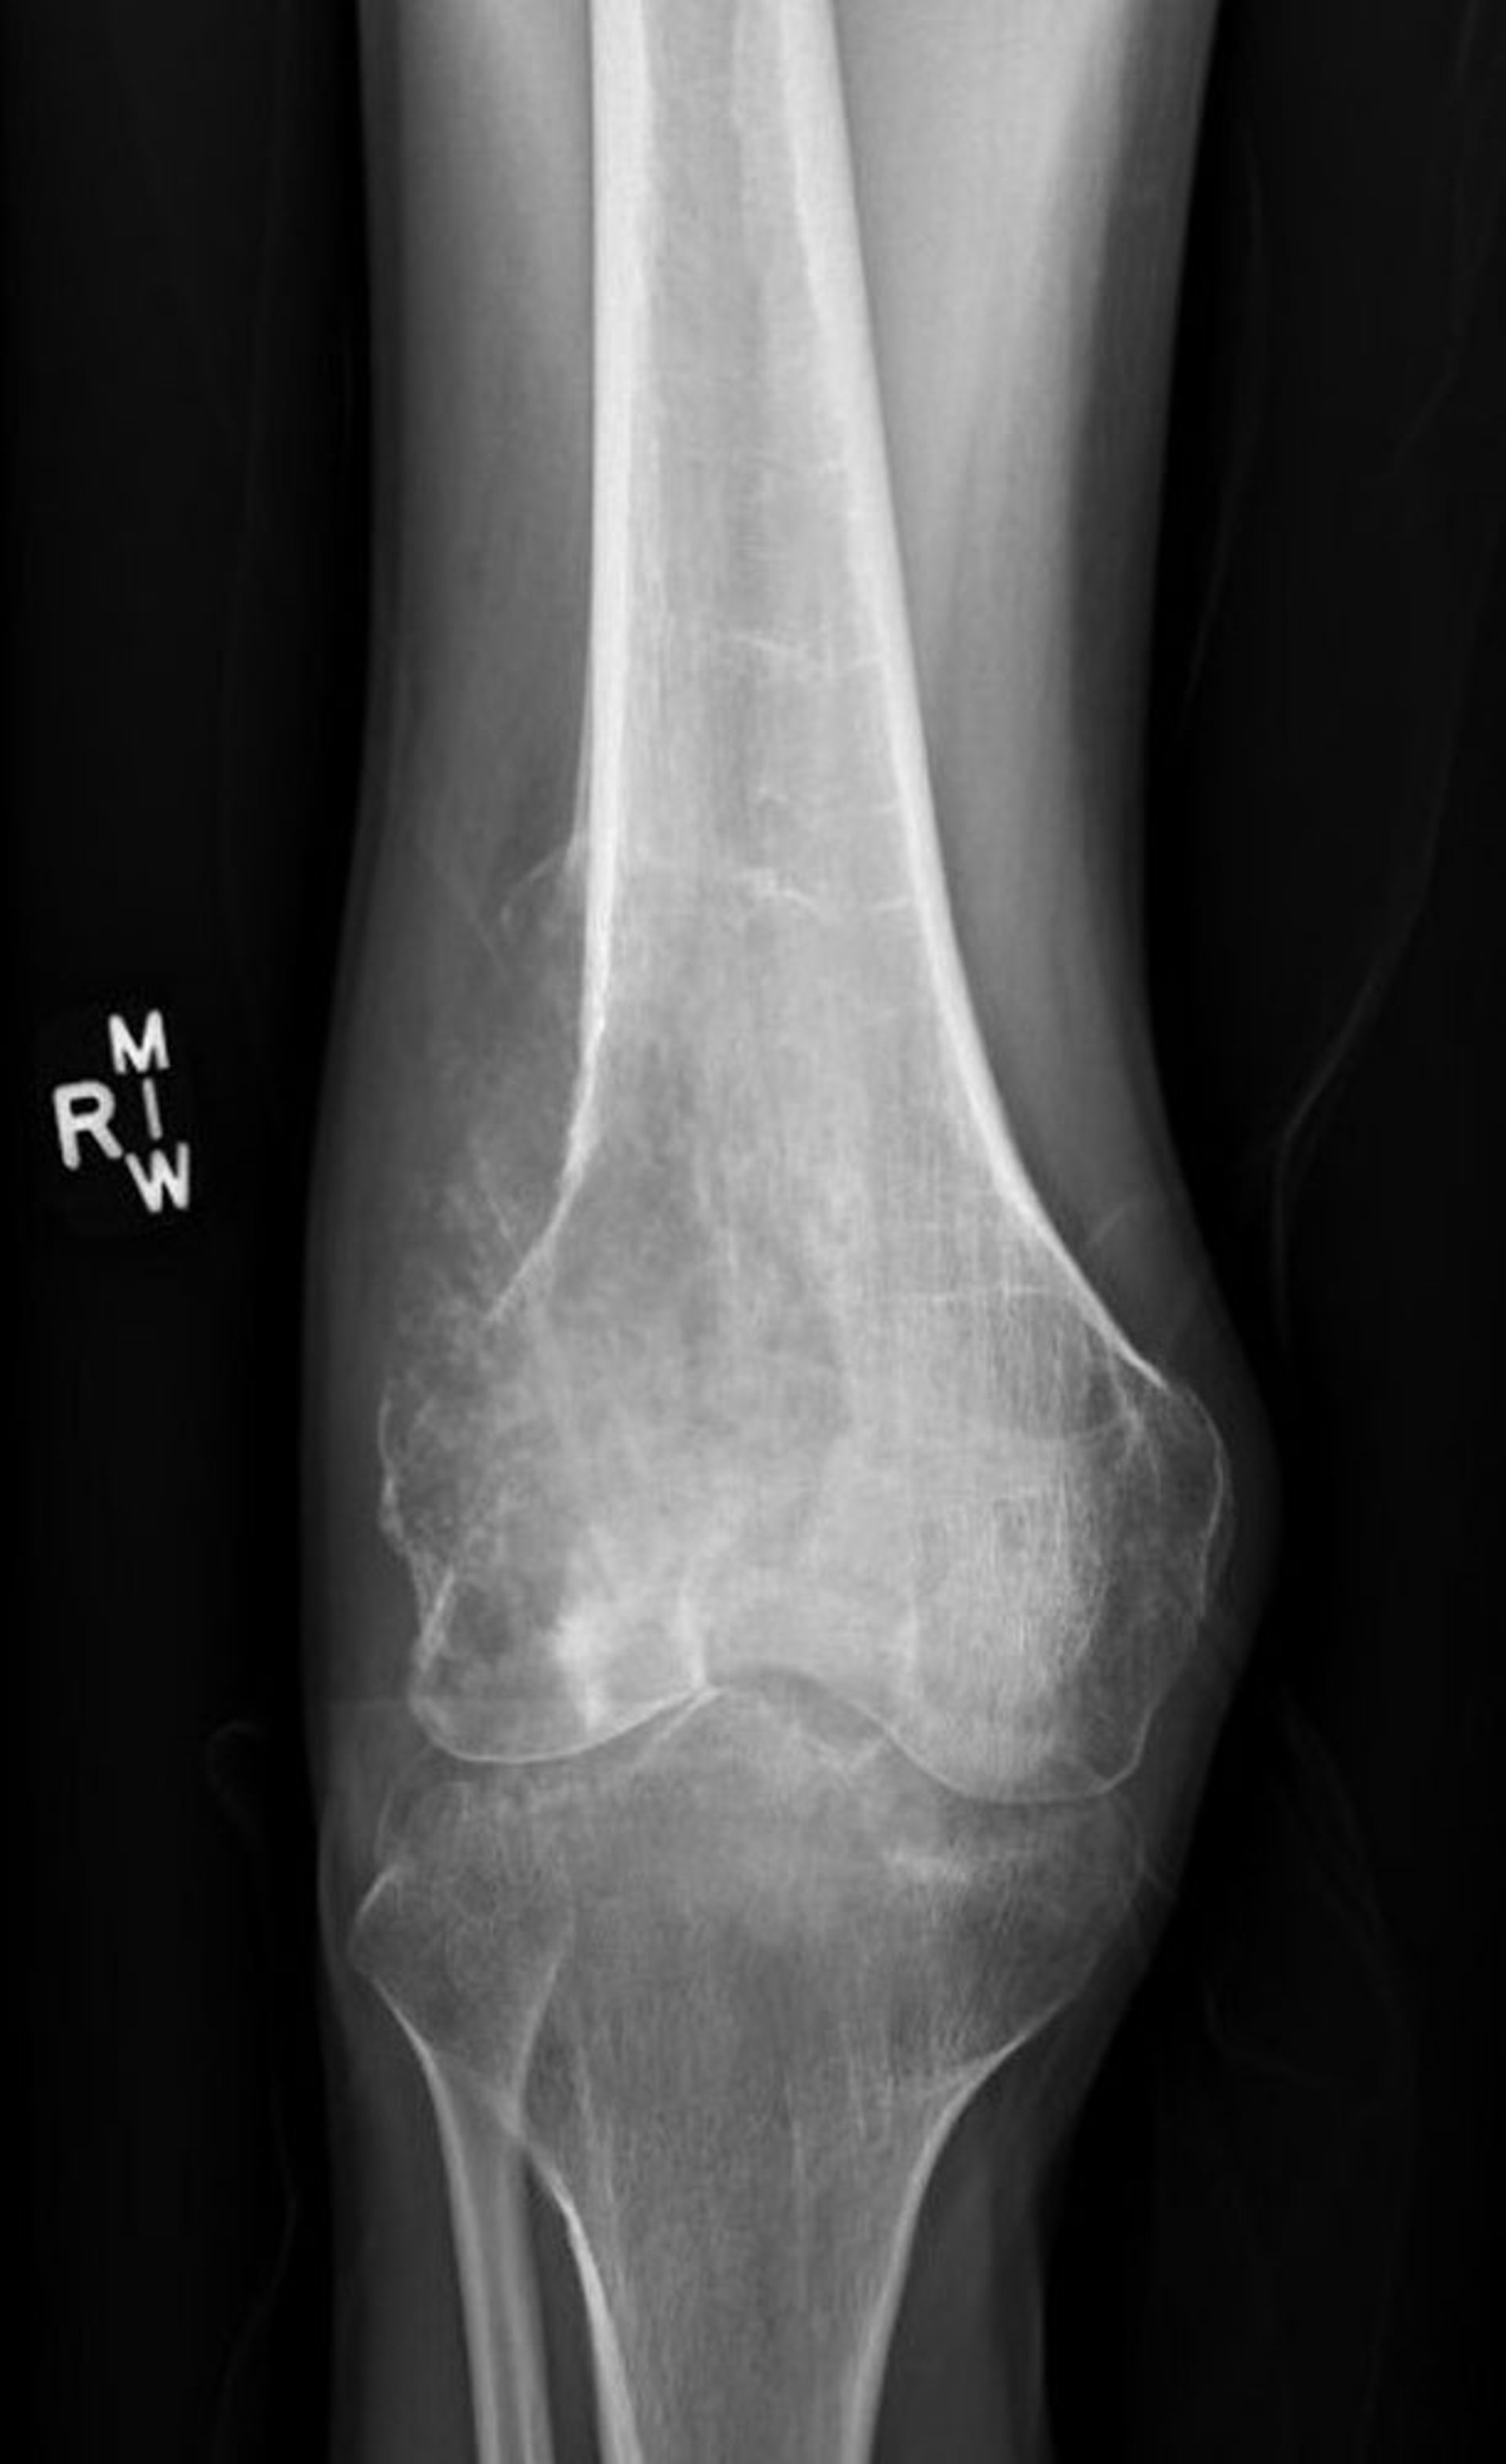

This x-ray of the knee shows an osteosarcoma in the thigh bone (femur) above the knee.

Image courtesy of Lukas Nystrom, MD.